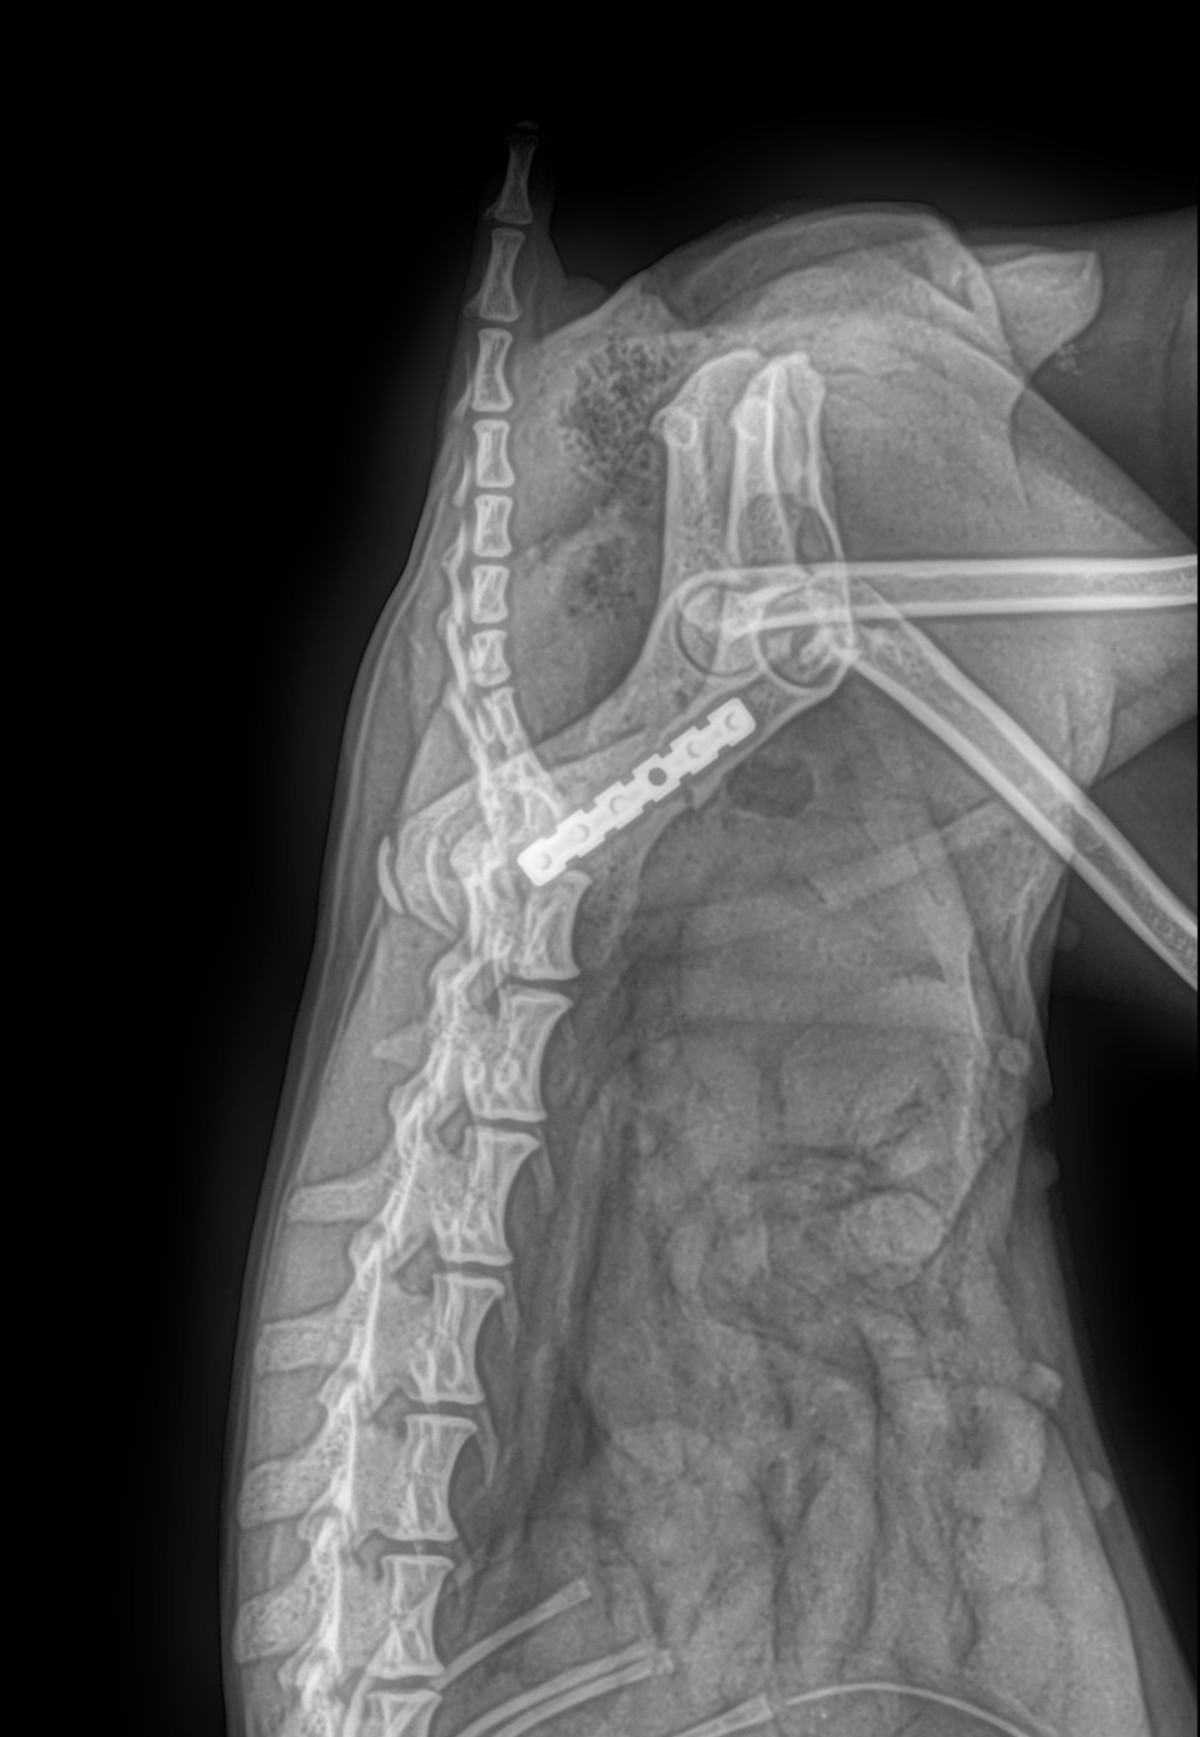

Radiología Digital como Herramienta Complementaria en el Dictamen de Bienes Muebles